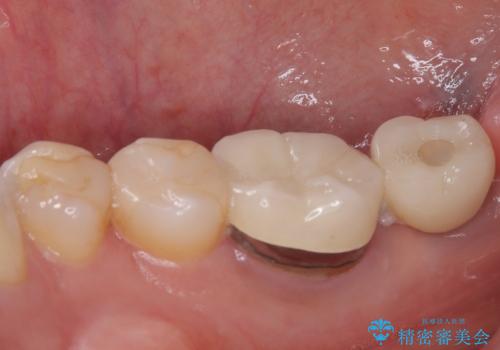

放置した奥歯 部分矯正を併用したインプラント補綴治療

- 右下欠損部のインプラント治療を希望して来院された患者様です。

右下の欠損部を長期間欠損を放置していたことで、咬み合う上の奥歯が動いてしまっていたので、まずは上顎奥歯の部分矯正を行うこととしました。

理想的な咬み合わせに改善した上で、インプラント補綴治療を行うこととしました。

部分矯正を行ったこと治療期間は長くなりましたが、違和感のない咬み合わせを達成することができました。